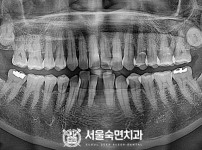

임플란트-전후사진2

임플란트-전후사진3